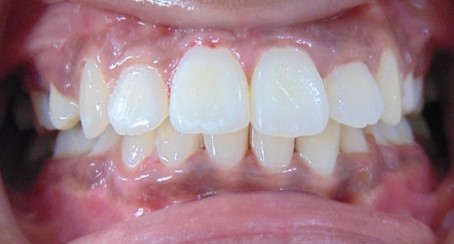

Kriti Sonal, 26Y, Duration - 8Months

Before

After

Image 1